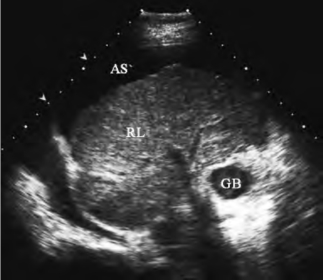

图23-7 肝硬化声像图

肝硬化的肝脏表面不平,实质回声增粗增强,伴肝前腹水

2.肝脏表面不平,呈锯齿状或波浪状,肝前有腹水时显示更清晰;肝缘变钝。

3.肝脏内部回声多表现增粗和增强,分布不均匀。有时见网状高回声的分隔。有的再生结节显示局限的低回声区。

4.肝静脉可受挤压变细或粗细不均匀。